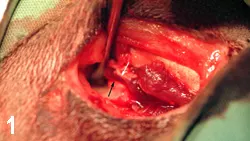

The ProcedureThe TMJ was approached through a lateral skin incision along the caudoventral margin of the zygomatic arch. A periosteal elevator was used to lift the condylar head (Figure 1; black arrow) into the temporal fossa (white arrow). The masseter muscle was reflected ventrally, and the damaged TMJ joint capsule was visualized by having an assistant open and close the jaw. The dorsocranially deviated condyle was reduced into the temporal fossa. A small hole was drilled through the lateral condyle and fossa by using a no. 1 round bur in a high-speed dental handpiece. A 4-0 nonresorbable nylon was threaded through the predrilled holes, and a simple interrupted knot was tied (Figure 2). Because there was no overlying musculature around the severely damaged joint capsule, imbrication was impossible. A postreduction extraoral radiograph indicated successful reduction (Figure 3).